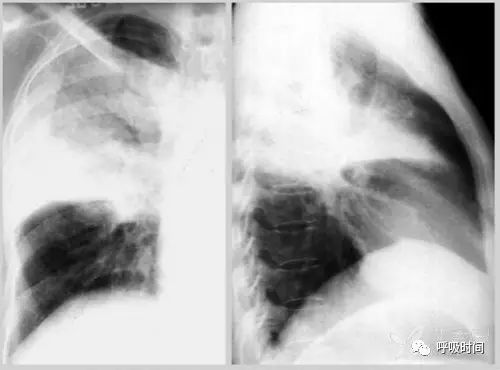

图 3 胸部正位片:右肺栓塞。片示右中肺野血管纹理减少,密度减低(黄箭头);红箭所示为正常肺纹理。